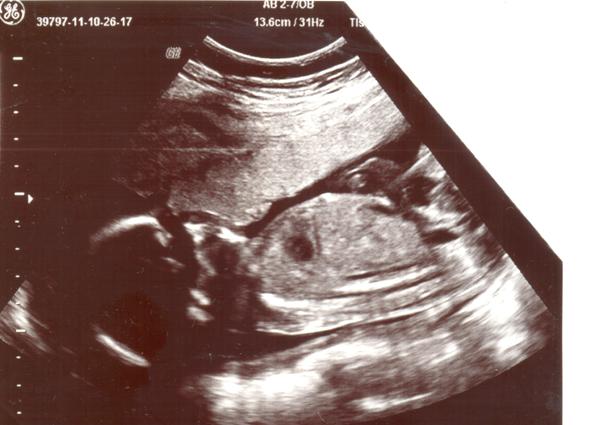

Attached is 20 wk ultra sound.

Did'nt want to find out at time of scan but now I kinda do!

Not sure is that a pee pee down around groin area or could it be the cord or something else?

Attachment 775

Any opinions appreciated - boy or girl?